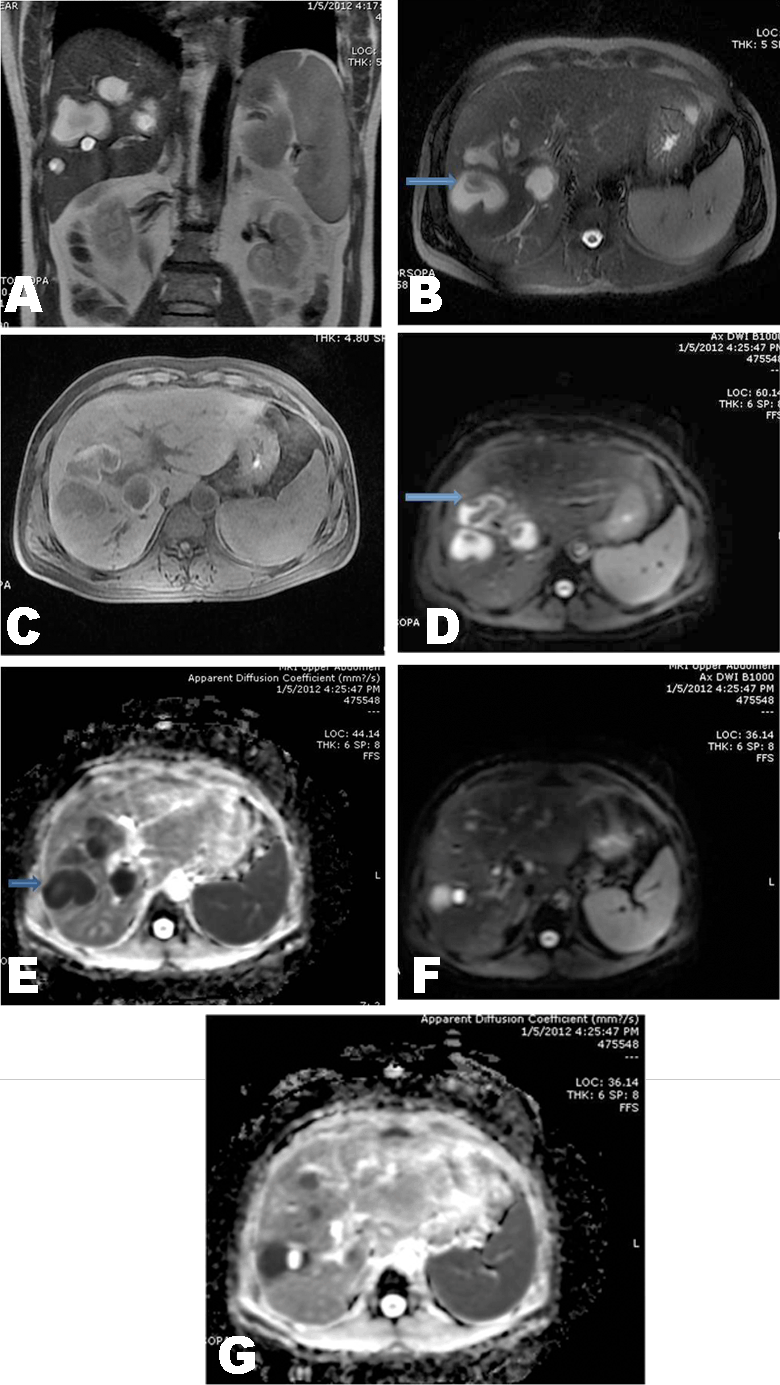

MRI scan showed conglomerating T2 hyperintense lesions with thick nodular regions along the walls (Figure 3A, B). T1 hyperintense rim of few of these lesions was noted (Figure 3C). On diffusion weighted sequence the abscesses showed hyperintensity at b value 1000 with corresponding restriction on ADC maps (Figure 3D-G). A diagnosis of parasitic eosinophilic abscesses was suggested and proven on ultrasound guided biopsy, which showed eosinophils and charcot leyden crystals with necrosis.

Figure 3: A) Coronal SSFSE T2 weighted sequence shows 3–4 cms lobulated rounded lesions with thick hypointense walls and hyperintensity within. Smaller one cm lesion is brighter than other lesions and is likely to represent a cyst, B) Axial T2 weighted SSFSE sequence showing similar lesions as in figure A, C) Axial T1 lava sequence showing well defined hyperintensity of the walls of the lesions. which are hypointense to rest of the liver; D, E) DWI at b value of 1000 showing bright lesions with hypointense nodular walls and corresponding restriction on the ADC maps; F, G) DWI at b value =1000 shows a smaller brighter lesion to the right of a mildly hyperintense larger lesion without restriction on corresponding ADC map (appearing bright on both images F and G) suggestive of a simple cyst.